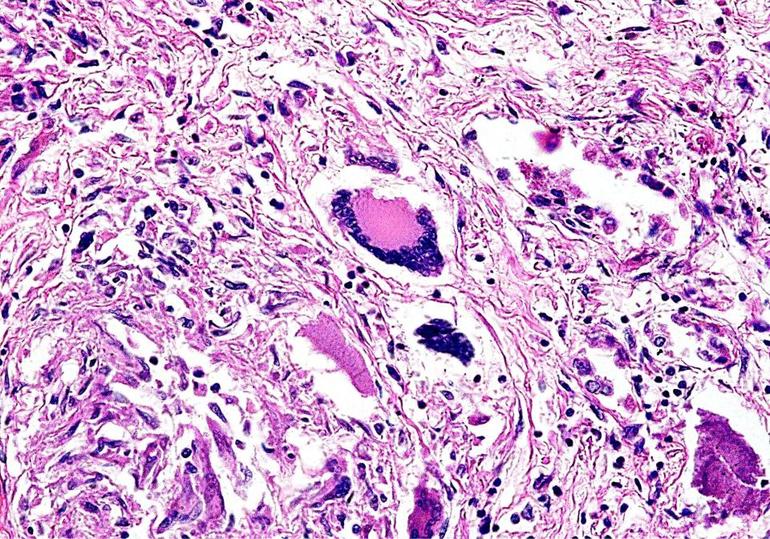

Заболевание начинается с образования аутоиммунных антител, которые атакуют здоровые клетки, приводя к их разрушению и воспалению тканей. Васкулиты чаще всего затрагивают эпителиоидные и гигантские клетки. Основным морфологическим признаком этого заболевания является гранулема — область некроза, окруженная инфильтратом, состоящим из нейтрофилов, плазмоцитов, лимфоцитов и эозинофилов.

При болезни Вегенера воспалительный процесс в стенках сосудов проходит три последовательные стадии: альтерацию, экссудацию и пролиферацию. Измененные участки поражения представляют собой скопления мелких гранул — гранулемы.

В какой-то момент каждая гранулема начинает распадаться, образуя кровоточащие полости на стенках сосудов — каверны. Этот процесс сопровождается образованием аневризм, которые могут разрываться, вызывая кровоизлияния. В подкожно-жировой клетчатке и внутренних органах развивается продуктивное воспаление микроциркуляторного русла, а на коже формируются язвы, вызванные некротическими гранулемами. У здоровых тканей отсутствует механизм защиты от агрессивных антител, что приводит к стремительному прогрессированию заболевания.